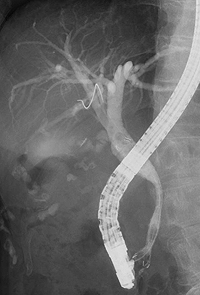

X線透視検査は、よく知られている胃のバリウム検査はじめ、食道、小腸、大腸といった消化管の癌の診断に用いられています。当院の透視装置は平面検出器(FPD: Flat Panel Detector)搭載X線TV装置であり、このFPD装置で撮影された画像は、直接、画像支援システムに送信され、各診療科で鮮明な画像を見ることが可能となりました。他に、電子内視鏡装置を併用して胆道・膵管を造影する内視鏡的逆行性胆道膵管造影(ERCP: Endoscopic Retrograde Cholangio-Pancreatography)も行っており、膵・胆道系の癌の診断に役立っています。閉塞性黄疸に対しては、ステント留置術も行っています。

| 膵癌に対する胆道ステント留置術 | |